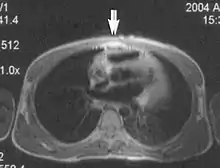

Fig. 10. Surface coil artifact: high signal at anterior thoracic wall adjacent to surface coil.[1]

Surface coil artifacts

Close to the surface coil the signals are very strong resulting in a very intense image signal (Fig. 10).[1] Further from the coil the signal strength drops rapidly due to the attenuation with a loss of image brightness and significant shading to the uniformity. Surface coil sensitivity intensifies problems related to RF attenuation and RF mismatching.